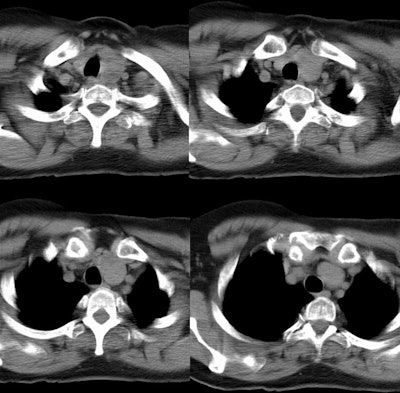

Mediastinal goiter

The CT scan below demonstrates abnormal enlargement of the left lobe of the thyroid gland which extends into the anterior mediastinum, posterior to the manubrium. There is deviation of the tracheal air column to the right.